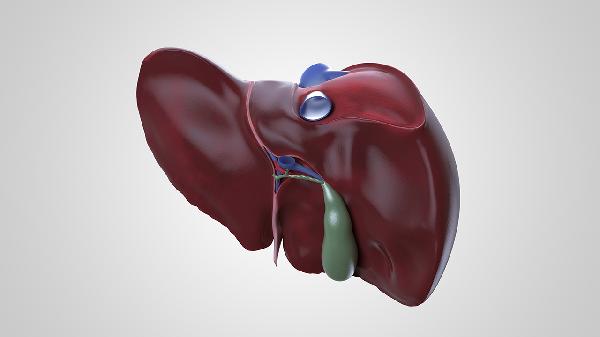

肝脏是体内糖原储存的主要器官,进食后血糖升高时,肝脏将葡萄糖转化为糖原储存;空腹时则分解糖原释放葡萄糖入血。这一动态平衡依赖肝细胞内的糖原合成酶与磷酸化酶活性调节。若肝脏功能受损,可能导致餐后血糖波动加剧或空腹低血糖。

肝脏是胰岛素的主要靶器官,通过抑制糖原分解和糖异生降低血糖;同时响应胰高血糖素促进糖原分解。胰岛素抵抗时,肝脏对胰岛素的敏感性下降,可能导致空腹血糖持续升高,成为2型糖尿病的重要发病机制。

肝脏脂肪堆积(如非酒精性脂肪肝)会干扰胰岛素信号传导,加重胰岛素抵抗。此外,肝脏合成的极低密度脂蛋白增多可能间接影响外周组织对葡萄糖的摄取利用,形成代谢紊乱的恶性循环。

病毒性肝炎、肝硬化等肝脏疾病常伴随糖代谢异常,表现为肝源性糖尿病。这类患者可能出现空腹血糖正常但餐后血糖显著升高的特征,与胰岛β细胞功能受损和肝糖输出增加有关。